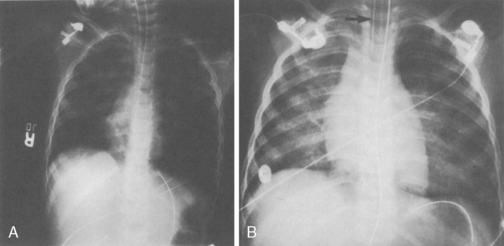

The chest radiograph of the child with BPD characteristically shows scattered linear infiltrates and patchy areas of hyperinflation (Fig. 9-16). Arterial blood gases usually reveal hypercapnia, mild acidosis (compensated respiratory acidosis), and mild hypoxemia.228,249 The child may have a barrel chest, tachypnea, retractions, wheezing, crackles, and failure to thrive. In severe forms of old BPD, digital clubbing may be present, which indicates a poor prognosis.

image

Fig. 9-16 The most common radiographic finding associated with bronchopulmonary dysplasia is the presence of diffuse infiltrates. These infiltrates produce a ground-glass or marbleized appearance in the lung fields. Emphysema may or may not be present.

(Courtesy Thomas A Hazinski, Vanderbilt University Medical Center, Nashville, TN.)